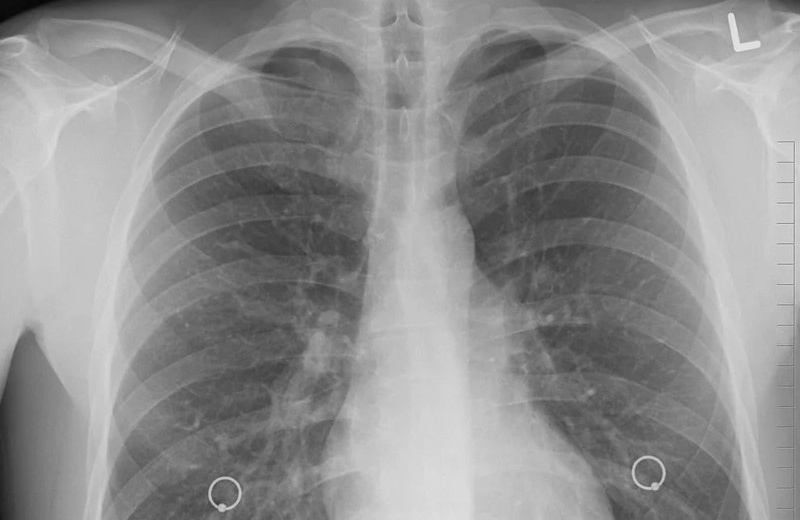

Фтизиатрическая служба Магаданской области работает в соответствии с общероссийскими стандартами и демонстрирует стабильные показатели. В регионе внедрены современные организационные, диагностические и противоэпидемические технологии, обеспечивающие соблюдение актуальных клинических рекомендаций. За 2025 год в области зарегистрировано 37 новых случаев туберкулёза, показатель заболеваемости составил 27,8 на 100 тысяч населения, что соответствует уровню предыдущего года. Благодаря профилактическим осмотрам 70,3% случаев заболевания выявлено на ранних стадиях, что существенно повышает эффективность лечения. Среди впервые выявленных пациентов — 34 взрослых, 1 подросток и 2 ребёнка, соотношение мужчин и женщин составляет 3:1, средний возраст заболевших — 44 года. Особое внимание специалисты уделяют работе с медико-социальными группами риска: 64,8% заболевших относятся к категории неработающего населения. У 13,8% впервые выявленных пациентов диагностировано сочетание туберкулёза и ВИЧ-инфекции (по Российской Федерации — 24,3%), данная категория пациентов находится под постоянным контролем специалистов.

Эпидемиологическая ситуация по туберкулёзу в Магаданской области в 2025 году оценивается как стабильно благополучная, показатель заболеваемости сохраняется ниже уровня допандемийного периода. В регионе реализуется системный подход к раннему выявлению заболевания: профилактические осмотры прошли 82,6% населения — 109 375 человек, охват иммунодиагностикой (проба Манту, Диаскинтест) детского населения составил 98,7%. Отмечена положительная динамика в ответственном отношении родителей к здоровью детей: количество отказов от иммунодиагностики снизилось на 38%, всё больше семей выбирают современные и безопасные методы ранней диагностики туберкулёза у детей.

Туберкулёз относится к числу заболеваний, которые легче предупредить, чем лечить. Своевременное прохождение профилактических осмотров — флюорографии для взрослых и иммунодиагностики для детей — позволяет выявить заболевание на ранней стадии, что гарантирует полное излечение и предотвращает распространение инфекции среди близких. Жителям Магаданской области рекомендуется ежегодно проходить диспансеризацию, а при появлении таких симптомов, как длительный кашель, слабость, потеря веса или субфебрильная температура, незамедлительно обращаться к врачу.